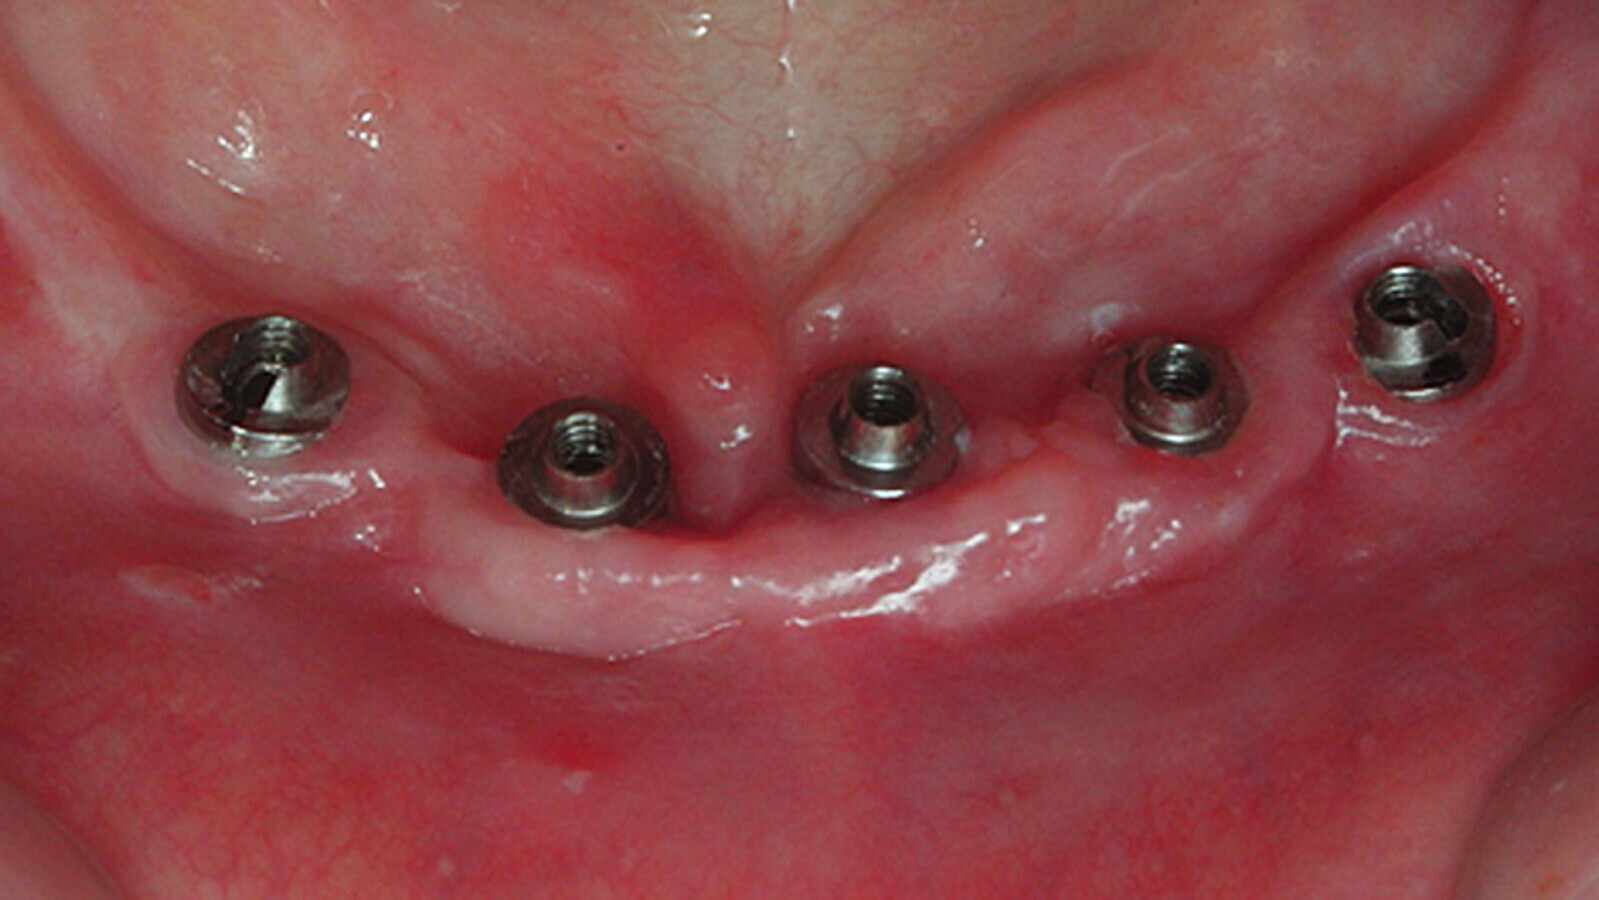

Fig. 2. Colocación adecuada de implantes salvando los músculos mentonianos.

En líneas generales, se colocan entre 4 y 5 implantes en la arcada inferior y 5 o más en la superior, buscando asentar fijaciones de más de 10 milímetros de longitud con diámetros que varíen entre 3.3 y 4.2 milímetros. Los mismos debería estar distribuidos generando el mejor polígono de sustentación posible, y salvando las estructuras anatómicas nobles del área (dentario inferior y seno maxilar superior). El paralelismo entre los implantes debería ser adecuado, aunque algunas técnicas preconizan la posibilidad de colocarlos angulados (ejemplo All-on-4, 5 ó 6), de forma que se pueda proteger órganos importantes. Si la distribución y ferulización de los implantes es adecuada, se permiten pónticos a extensión distal de hasta de 13 milímetros sin que se comprometa la biomecánica del aparato.

Fig. 4. Sistema Multiunit colocado en boca.